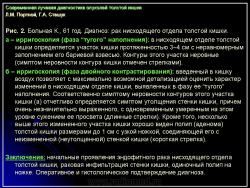

Основными симптомами внутристеночного опухолевого поражения в фазу “тугого” наполнения толстой кишки при ирригоскопии являются:

1. Сужение просвета кишки и соответственно этому неровность контура на небольшом протяжении, требующие подтверждения с помощью двойного контрастирования, выявляющего на этом уровне симптом утолщения стенки кишки (рис. 2).

В фазу двойного контрастирования толстой кишки более четко определяются симптомы сужения просвета участка кишки и соответственно этому локальное или распространенное утолщение стенки. Достоверность всех вышеперечисленных симптомов внутристеночно растущего рака толстой кишки резко увеличивается, если их локализация в кишке идентична как в фазу ее “тугого” наполнения, так и при двойном контрастировании.